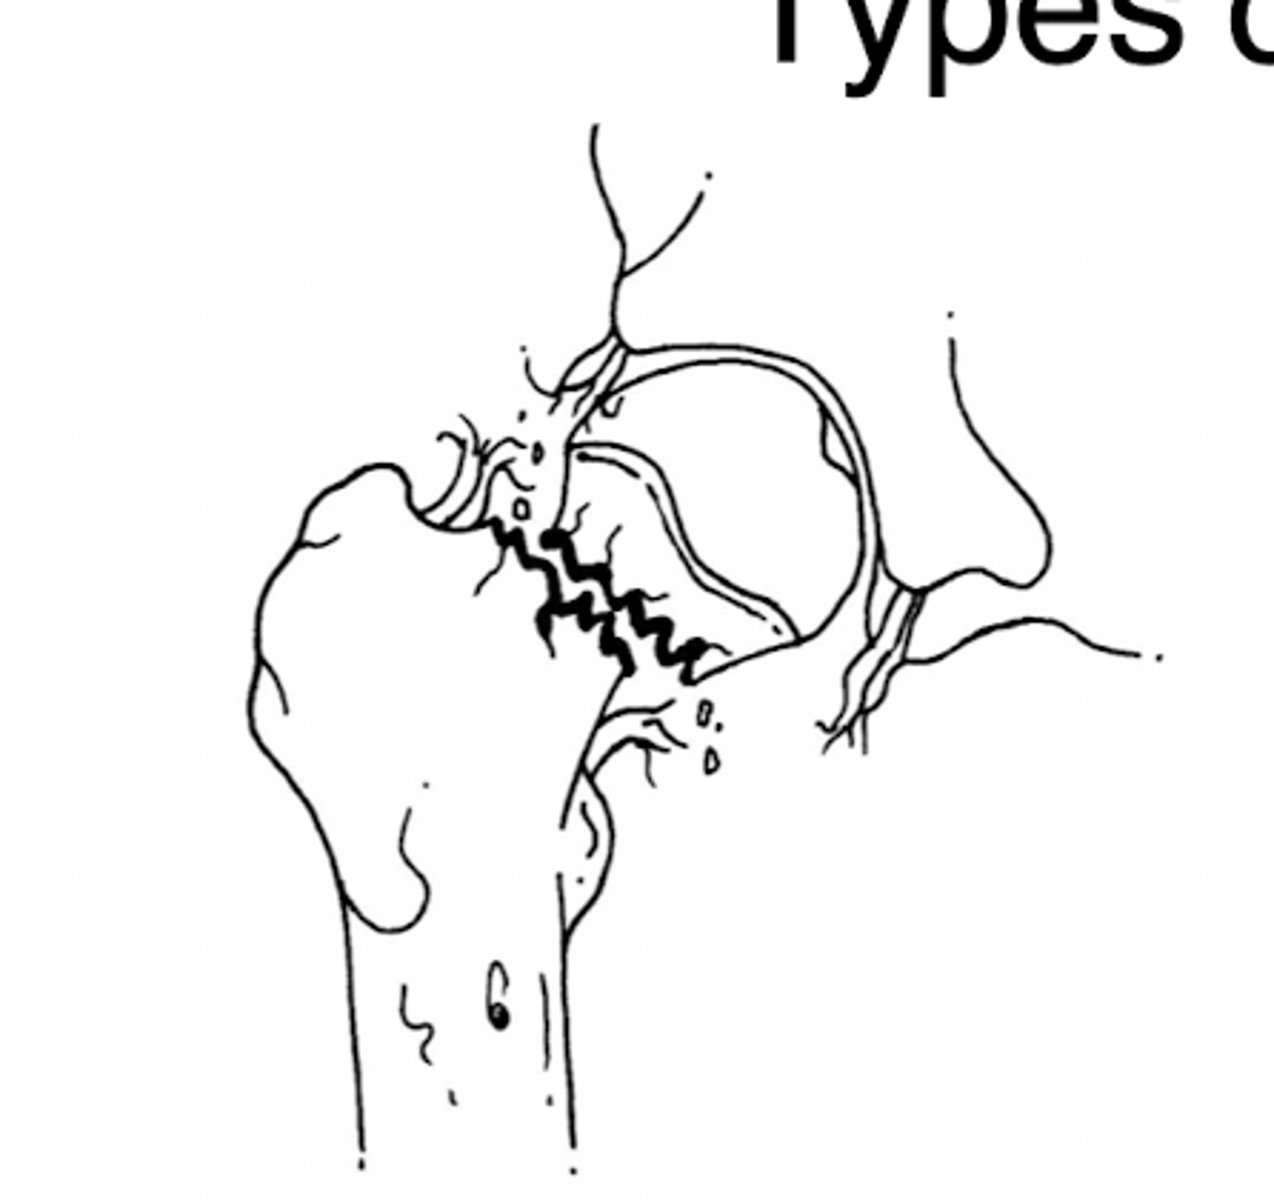

intertrochanteric fx

intertrochanteric fx

Comminuted intertrochanteric fracture. There is a fracture from the greater to the lesser trochanter (blue arrow). There are separate fragments of the greater trochanter (white arrow) and lesser trochanter (red arrow). There is varus deformity (white line) of the femoral shaft.